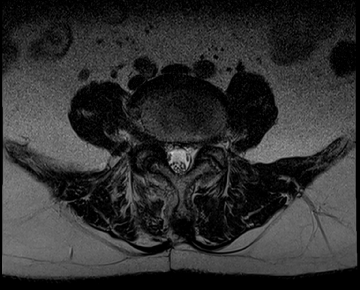

요추 협착증 수술 전·후

2020.08.30

2022.09.06

ㆍ환자 동의를 받은 자료이며, 이미지 사진은 실물과 다를 수 있습니다.

ㆍ모든 자료는 새움병원 자료입니다.